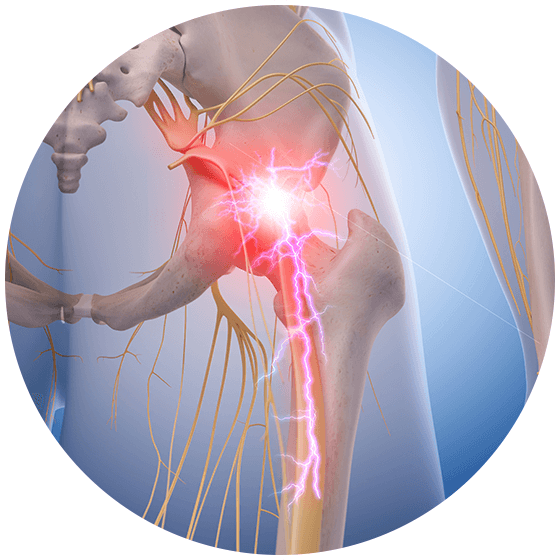

Download Sciatic nerve pain pictures